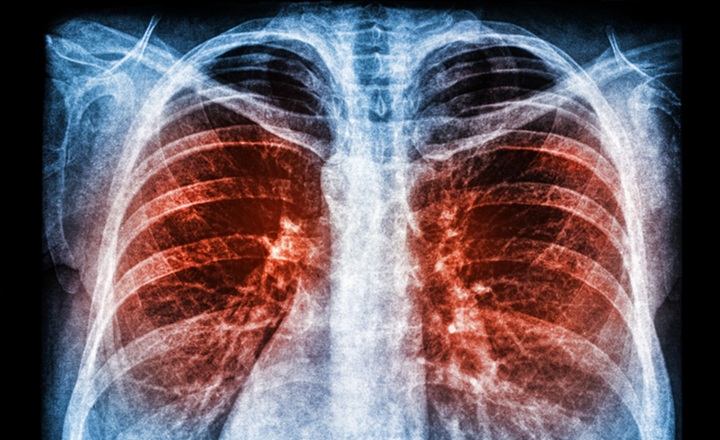

• High mortality condition: severe community-acquired pneumonia (SCAP) remains a leading cause of ICU admission and death, requiring rapid pathogen identification and targeted therapy.

Key Findings:  Sun et al. conducted a retrospective study involving 397 ICU patients with SCAP who underwent both bronchoalveolar lavage fluid (BALF) mNGS and conventional microbiological testing.¹ Patients were stratified based on timing of antibiotic modification: early (≤72 h) vs late (>72 h).

• Superior pathogen detection: metagenomic next-generation sequencing (mNGS) significantly outperformed conventional tests (92.7% vs. 57.2% detection rate) and was particularly effective for mixed infections (51.6% vs. 19.1%).

• Mortality benefit: Early mNGS-guided antibiotic adjustment (≤72 h) significantly reduced 28-day mortality compared with delayed adjustment (41.98% vs. 53.76%). The benefit was more pronounced in immunocompromised patients (39.29% vs. 60.00%).

• Independent protective factor: Early adjustment remained independently associated with improved survival (adjusted OR ~0.44).

Bigger Picture: This study underscores a key principle for clinical microbiology and antimicrobial stewardship: diagnostic results alone do not improve patient outcomes—timely clinical action is essential. Metagenomic next-generation sequencing (mNGS) provides a sensitive, unbiased method for pathogen detection, but its utility depends on rapid integration into therapeutic decision-making. Delays in acting on sequencing results can substantially diminish its clinical impact. These findings support a workflow that combines real-time diagnostics with immediate stewardship intervention, particularly for high-risk populations such as immunocompromised patients. As sequencing technologies become more widely implemented, optimizing turnaround time and clinical decision pathways will be as important as analytical performance in realizing their full clinical benefit.